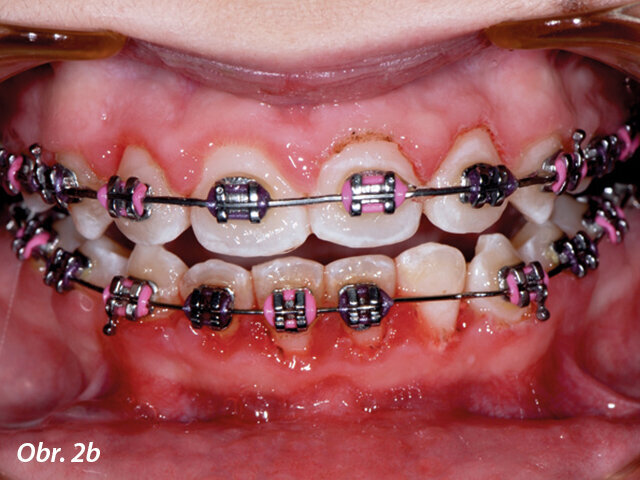

Gingivoplastika týden po operaci.

Částečně prořezaný zub může často zpomalit průběh celé terapie. Recontouring dásní umožňuje správné umístění zámku a okamžité zahájení zařazování zubu ortodontickým aparátem. Nedostatečně prořezaný zub částečně krytý gingivou může být častěji postižen dekalcifikacemi, protože v průběhu terapie pacient není schopen vyčistit sklovinu v místě gingivální hyperplazie. Odvápnění v obtížně dostupných oblastech může ohrozit výsledky celé léčby. Po ukončení ortodontické terapie mohou být pro zlepšení estetiky laserem odstraněny zduřelé dásně, vždy však pouze v rámci biologických limitů (obr. 2–4).